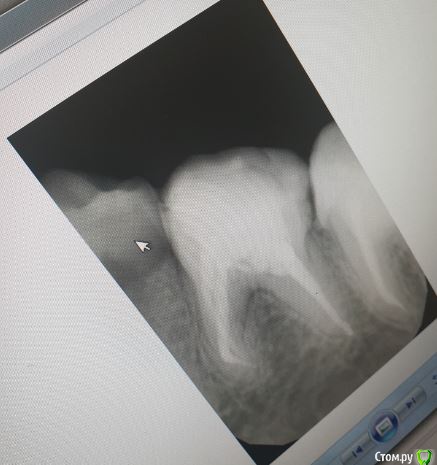

Vords Опубликовано 11 июня, 2020 Поделиться Опубликовано 11 июня, 2020 (изменено) Доброго вечера, профессионалы. Прошу у Вас помощи. Буду очень благодарен за консультацию. 3 недели назад появились боли в в жевательных зубах (около 37 и 36 зубов). В виду того, что боли были достаточно серьезные, а врач, у которого я лечился ранее не мог меня принять из-за пандемии - пришлось идти в городскую поликлинику. По результатам похода был поставлен диагноз пульпит 37 и глубокий кариес 36. На 36 поставили пломбу - 37 успешно депульпировали. На этом история 37 зуба закончена. С 36 после постановки пломбы начались дикие ночные боли и боли при накусывании. На повторном приеме был поставлен диагноз пульпит 36 - поставлено лекарство для умертвления нерва. После этого боль при накусывании прошли. В следующий прием пришел на чистку каналов и пломбировку. Во время этой процедуры я вдруг ощутил совершенно дикую боль (как выяснилось потом - в этот момент и произошла перфорации в области фуркации). Врач ничего не сказал - просто поставил метапекс и запломбировал каналы. В этот момент начались боли при накусывании. а потом постоянная тянущая боль. Продолжалось это около 3 дней - я пошел в другую стоматологию где мне сделали рентген и с подозрение на перфорацию отправили на КТ. По результатам КТ перфорация была подтверждена. С КТ я пришел в городскую стомотологию где мне предложили закрыть перфорацию цементом (pro что-то там - не могу сказать точно). Закрыли ее во вторник на этой неделе. Сегодня восстановили коронку и поставили световую пломбу. Беда в том, что боль при накусывании и "нытье" с этой стороны так и не прошли. По словам стомотолага гос клиники - боль при накусывании из-за метапекса и когда он рассосется - боль пройдет. (до 6 месяцев). Я прилагаю рентген (ужасное качество), фото КТ и ссылку в облако на КТ. Я допускаю, что никто не захочет лезть в облако и тратить свое время на просмотр на КТ (сам не могу разобраться с программой, что бы сделать достойные скрины), но если вдруг у кого-то найдется время - буду очень благодарен. Рентген сделан сразу после пломбировки канала. КТ через 3 дня после этого. В связи с этим вопрос. Возможно ли, что боль при надавливании пройдет если подождать пока рассосется метапекс или это пустая трата времени? Мне стоит ждать какое - то время или в этой ситуации мне поможет только удаление? Благодарю Вас за уделенное время Ссылка на КТ https://cloud.mail.ru/public/44WE/2JeTfXmr2 Изменено 11 июня, 2020 пользователем Vords Ссылка на комментарий

krokomot Опубликовано 11 июня, 2020 Поделиться Опубликовано 11 июня, 2020 Судя по всему у вас в 6м зубе выведен не только метапекс но и гуттаперчевый штифт, скорее всего, если это не исправить боли сохранятся, и что там с коронкой не понятно, на кт сильные тени из-за большого объема рентгеноконтрасного материалла, а прицельный снимок что вы сделали, сделан не поп правилам и на нем сильные искажения, понять трудно что с коронкой. Короче, зуб с перфорацией , выведенным материалом за апексом и гуттаперчей, и при этом еще и беспокоит, прогноз сомнительный. возможно всё можно переделать и всё станет нормально , но это не точно. Вам нужен грамотный доктор эндодонтист. 1 Ссылка на комментарий

Vords Опубликовано 12 июня, 2020 Автор Поделиться Опубликовано 12 июня, 2020 Да прицельный качественный подтвердит наличие штифта за апексом Доброго дня! Сделал прицельный еще один. По нему можно сделать какие-то выводы относительно наличия штифта? Благодарю за уделенное время. Ссылка на комментарий

krokomot Опубликовано 12 июня, 2020 Поделиться Опубликовано 12 июня, 2020 Да есть 2 Ссылка на комментарий